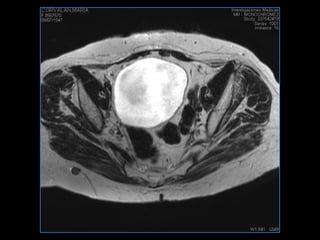

PROTOCOLO pelvis SAG T2, Y FAT SAT (FINOS) AXIAL T1  AX FAT SAT CON   GADOLINIO :  AX T1 Y COR T1 SAT: NO  FASE: RL THK: 3MM  COIL:  GAP: (FACTOR 1.4) 1MM FOV: 40 CM NEX:2 SINCRONIZACION RESPIRATORIA EN 3 O 4 CICLOS ALE

resonancia de abdomen